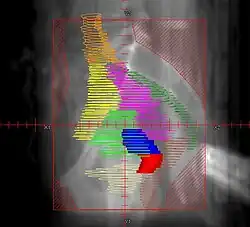

Example of an AP radiation therapy treatment field for Stage IB2+ Cervix used at Tufts/Brown residency program. Actual patient contours should guide field design.

• Superior border: L4/L5. If common illiac LN involvement, superior border should extend to L3/L4 or higher to cover the disease with 3 cm margin

• Inferior border: inferior edge of pubic ramus. If vaginal involvement, inferior border should extend 3-4 cm past the vaginal extent of the disease, as marked by a gold seed

• Lateral borders: ~2cm lateral to bony pelvis, in order to cover lymph nodes

• Red: cervix; Blue: uterus; Khaki: bladder; Brown: rectum

• Orange: common illiac LNs; Yellow: external illiac LNs; Light Green: obturator LNs; Purple: internal illiac LNs; Dark Green: presacral LNs